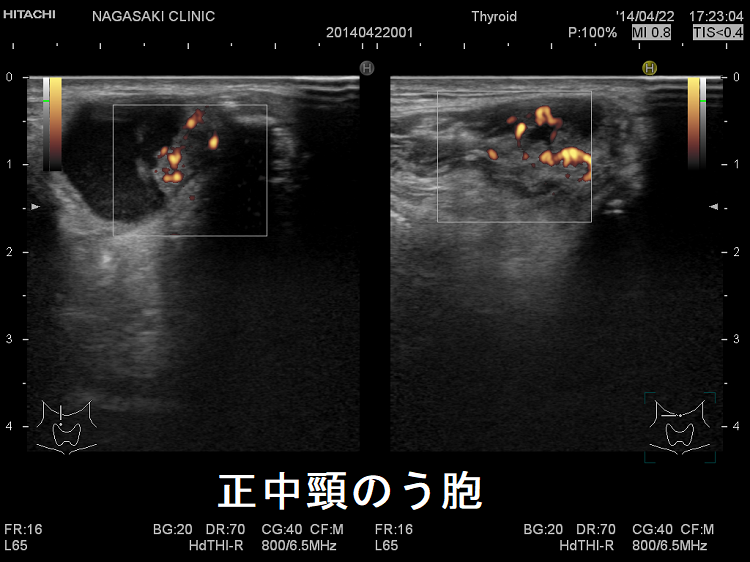

異所性甲状腺の一つ正中頸のう胞(甲状舌管嚢胞)

詳しくは、 正中頸のう胞(甲状舌管嚢胞) を御覧下さい。

正中頸のう胞 超音波(エコー)画像

正中頸のう胞 超音波(エコー)画像 ドプラー

正中頸のう胞(甲状舌管嚢胞) 超音波(エコー)画像 ドプラー